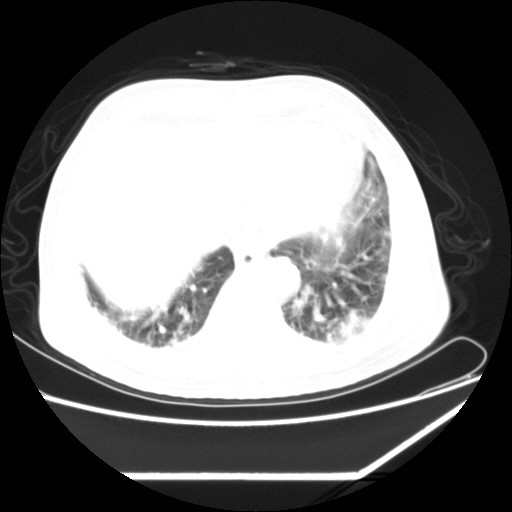

男,57,畏寒,发热

双肺多发结节样病灶,部分内见透光区,纵隔内见淋巴结肿大。结核临床如有畏寒,高热,白细胞增高首先考虑迁徙性肺脓肿(多是金黄色葡萄球菌感染)。

注意除外转移瘤。

双肺典型的亚急性粟粒性肺结核

双侧胸膜结核